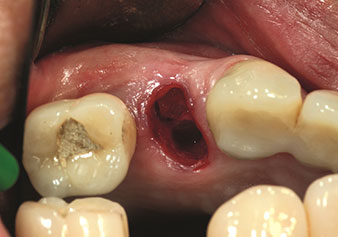

Endikasyon, dahili sinüs lifti

W&H ayrıca iç sinüs lifti için mükemmel bir çözüm sunar. Uygun aletlerle maksiller sinüs hazırlığından sonra

(Şekil 3), yeni uç Z35P (Şekil 4) ile membran hidrodinamik olarak kaldırılır. Aynı uç seti ayrıca Piezo cerrahisi yöntemiyle, artan çaplardaki implant yeri hazırlığı için de kullanılabilir [şekil 3 ve 4, Dr. Mario Kirste’nin (Frankfurt/Oder) onayı ile kullanılmıştır].